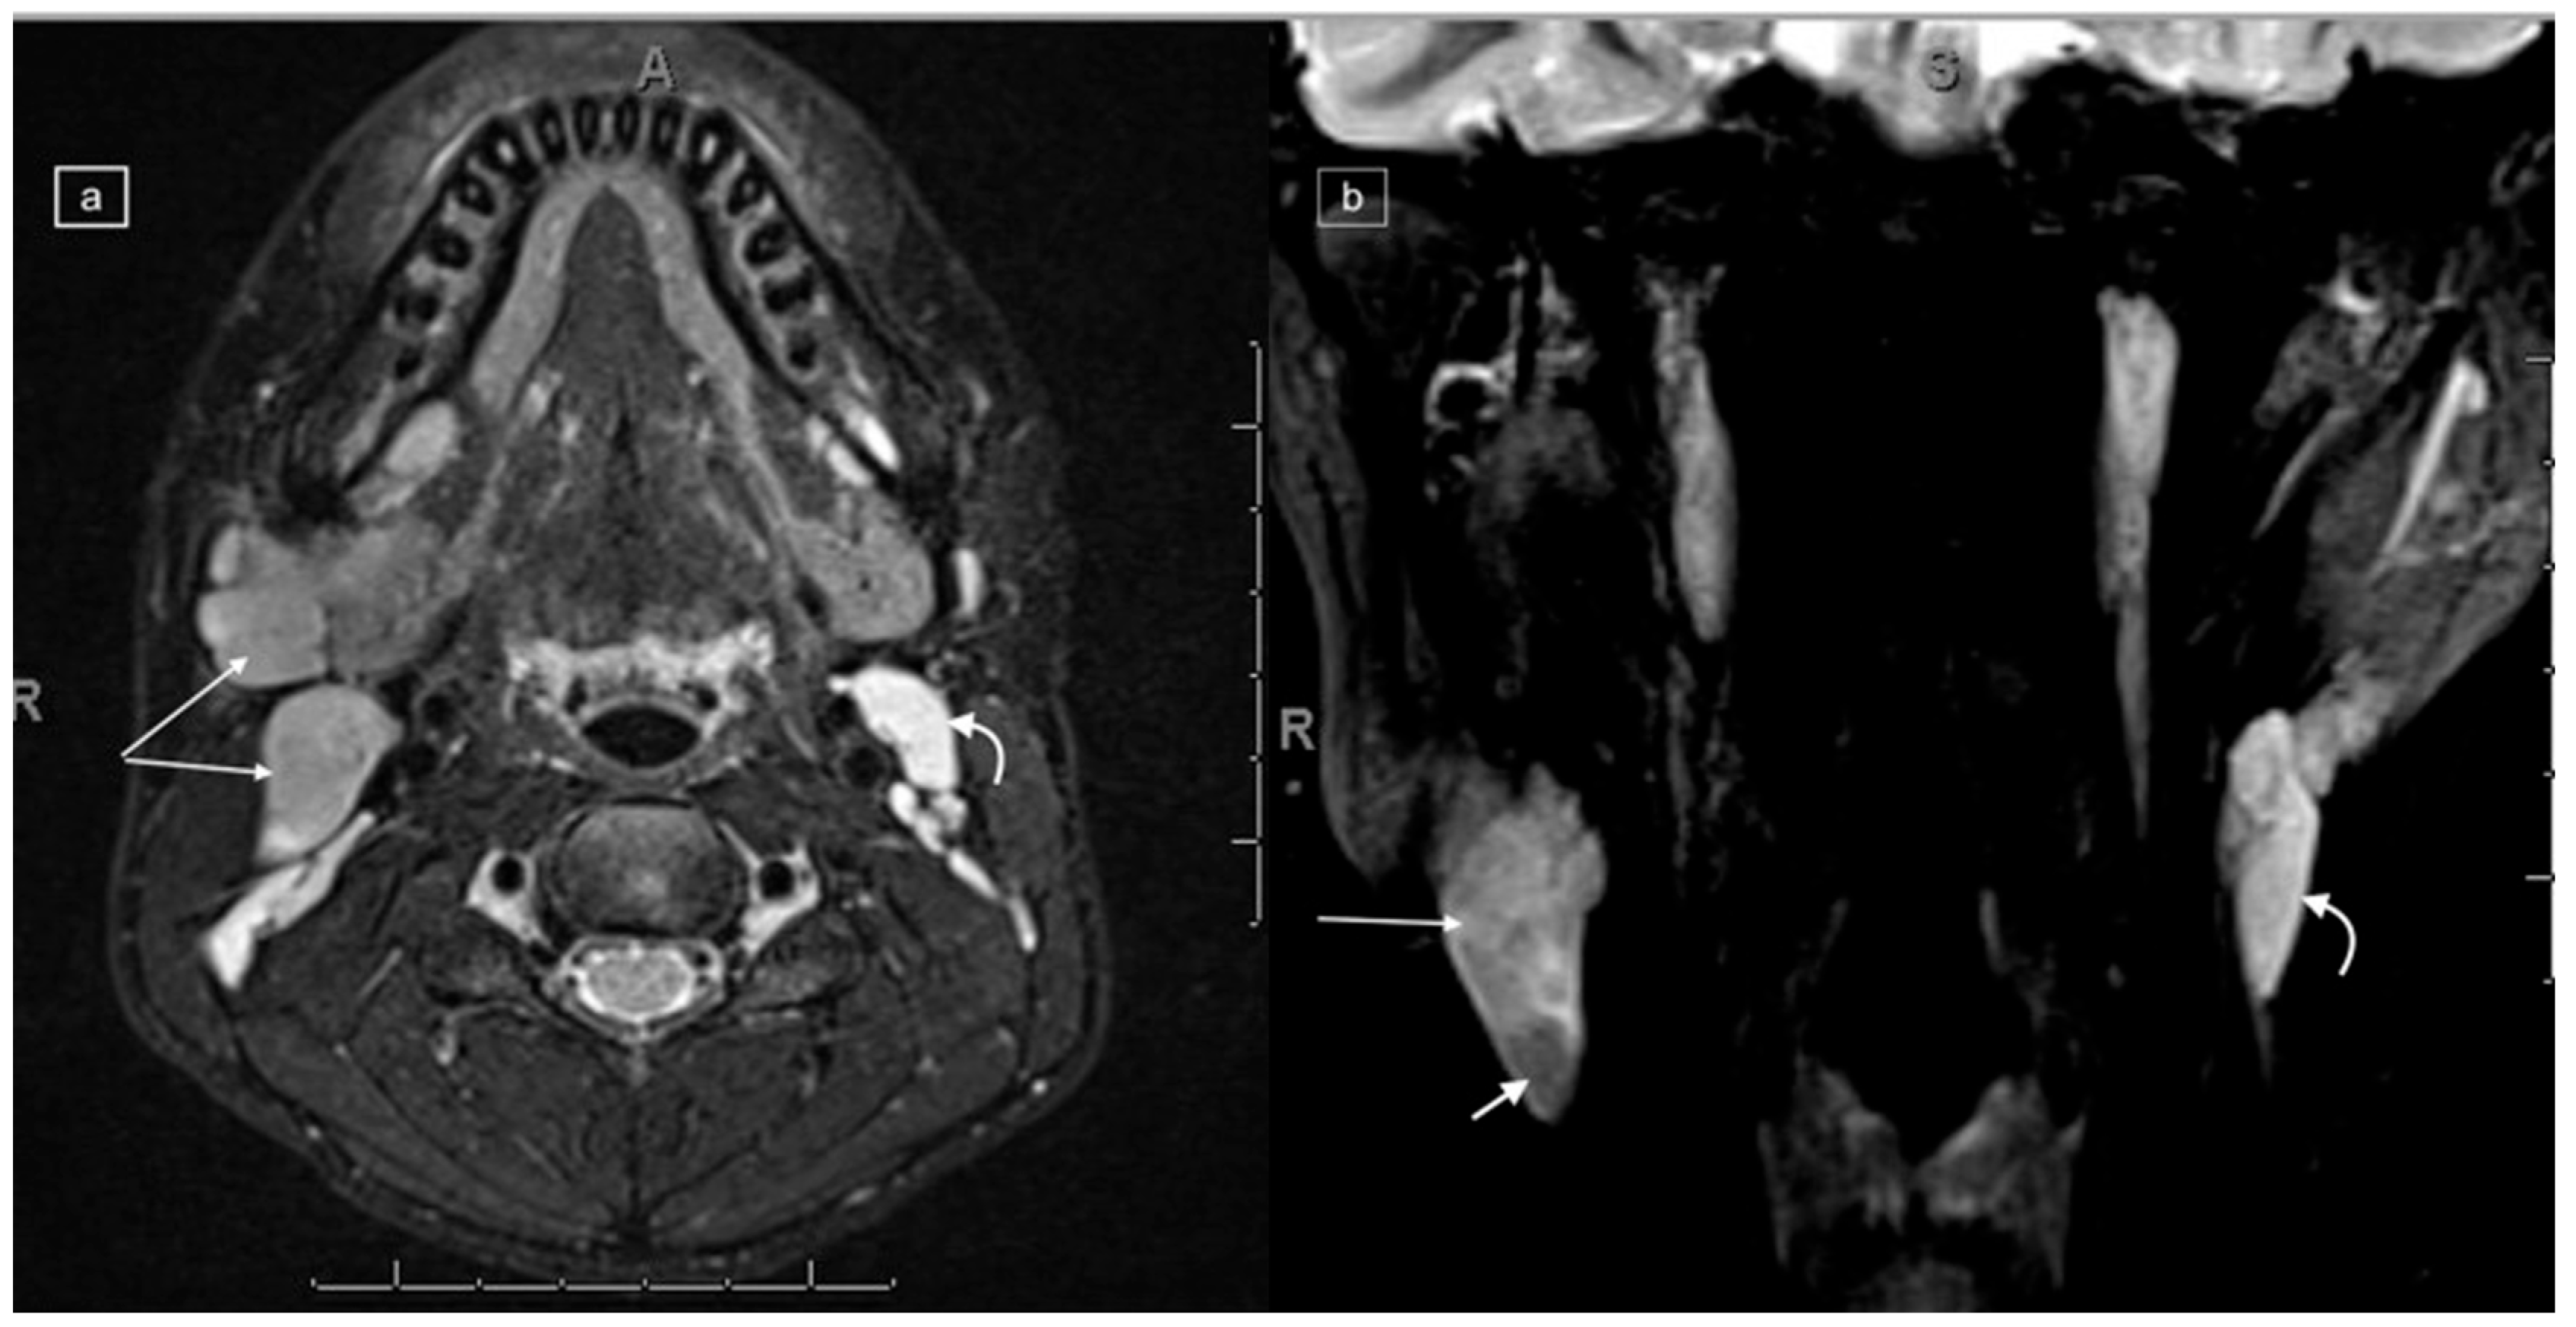

Figure 2.

Axial (a) and coronal (b) T2w DIXON MRI in a 16-year-old male with a histologic diagnosis of nodular sclerosing Hodgkin lymphoma, demonstrating right-sided lymphadenopathy with T2 isointensity (long arrows) as compared to the normal cervical nodes on the left demonstrating T2 high-signal intensity (curved arrows). In addition, there is a focal low-signal area within the largest lymph node on the right (short arrow in (b)).